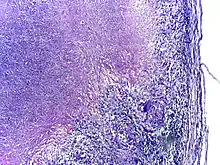

Tuberculosis is classified as one of the granulomatous inflammatory diseases. Macrophages, epithelioid cells, T lymphocytes, B lymphocytes, and fibroblasts aggregate to form granulomas, with lymphocytes surrounding the infected macrophages. When other macrophages attack the infected macrophage, they fuse together to form a giant multinucleated cell in the alveolar lumen. The granuloma may prevent dissemination of the mycobacteria and provide a local environment for interaction of cells of the immune system.[63] However, more recent evidence suggests that the bacteria use the granulomas to avoid destruction by the host's immune system. Macrophages and dendritic cells in the granulomas are unable to present antigen to lymphocytes; thus the immune response is suppressed.[64] Bacteria inside the granuloma can become dormant, resulting in latent infection. Another feature of the granulomas is the development of abnormal cell death (necrosis) in the center of tubercles. To the naked eye, this has the texture of soft, white cheese and is termed caseous necrosis.[63]